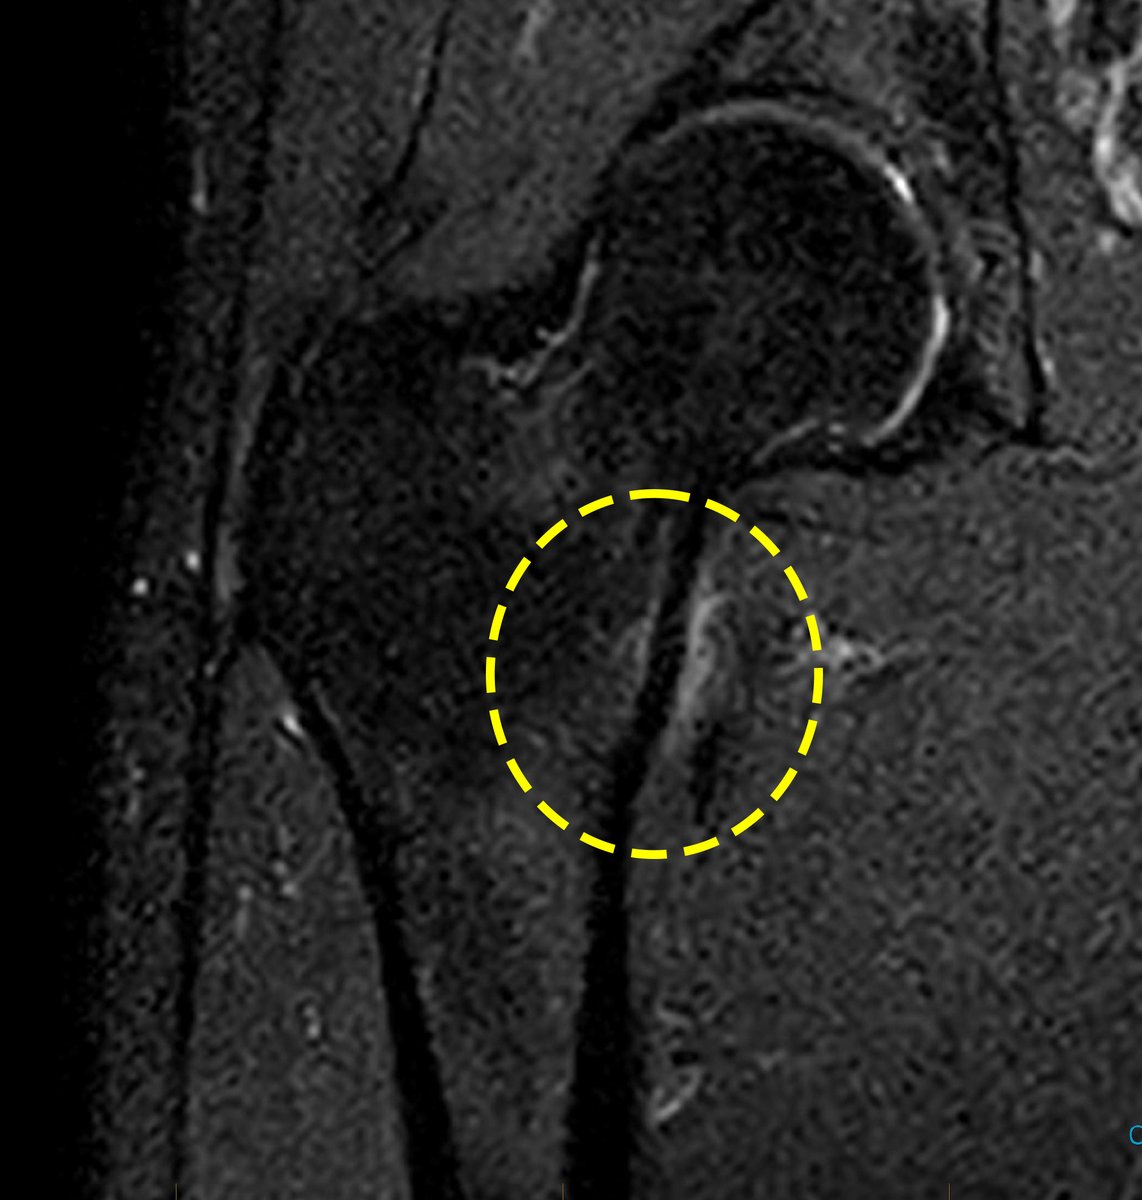

⚠️ Not all bone overuse injuries are stress fractures: it is time for updated terminology‼️NEW #Editorial 1️⃣ Should be referred to as "bone stress injuries" #BSI 2️⃣ Return to play may be affected by grade of injury 🏃♀️ 3️⃣ BSI location is important 🤔 👉 bit.ly/3O426N4